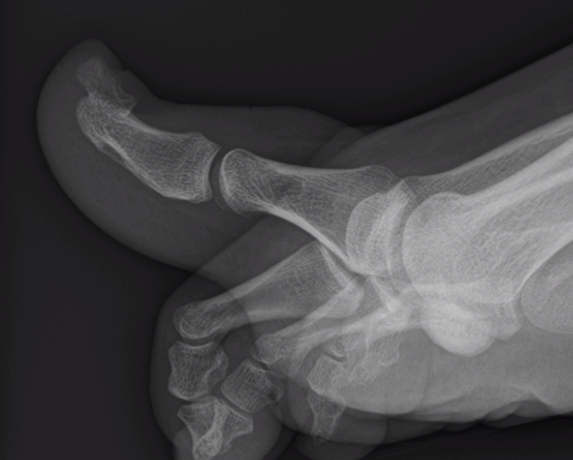

X-ray

Well defined bony mass arising from the surface of the bone

- no medulla